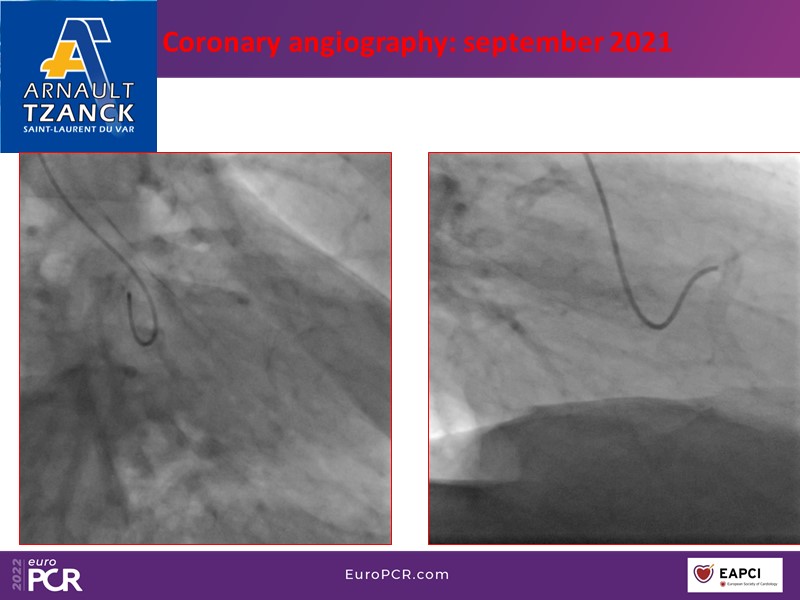

Looking at a 75-year-old male patient with HTA, diabetes, and hypothyroidism, a history of coronary artery disease treated with PCI of the RCA, and a previous coronary angiography showing preserved LVEF and in-stent restenosis of the RCA, you will learn in this EuroPCR 2022 session how to get started with the Reducer in your lab, get tips and tricks for implantation and understand how the therapy works.